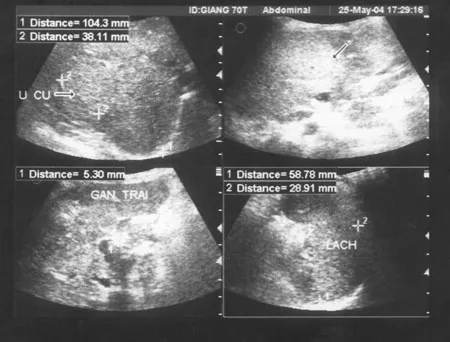

Ông Lê Đình Roanh – trung tâm nghiên cứu và phát hiện sớm ung thư – cho biết: Việt Nam chúng tôi đã sử dụng Curcumin điều trị có hiệu quả rất tốt cho một bệnh nhân u máu nội mô gan là một trẻ nhỏ 5 tháng tuổi. Bệnh nhân có nhiều u máu gan kích thước lớn (8 khối u) chiếm trên 60% thể tích gan.

Ảnh siêu âm trước điều trị (18/03/2003)

Lúc đầu chúng tôi đã liên hệ với nhiều trung tâm nhi khoa đều có một gợi ý là phẫu thuật ghép gan, chúng tôi đã thử điều trị bằng Curcumin thấy các triệu chứng rối loạn tiêu hoá, vàng da, chán ăn và gan to giảm nhẹ, trẻ phát triển thể lực tốt. Sau 1 năm kiểm tra lại bằng siêu âm tất cả các khối u của gan đã mất chỉ còn một vài vết sẹo nhỏ.

Ảnh siêu âm sau điều trị (05/2004)

Đây là trường hợp u máu nội mô gan ở trẻ còn ẵm ngửa lần đầu tiên và duy nhất điều trị hiệu quả bằng Curcumin được công bố trên y văn thế giới (http://www.ncbi.nlm.nih.gov/pubmed/20582974). Hiện nay cháu đã 8 tuổi, khoẻ mạnh, thông minh, học tập tốt.